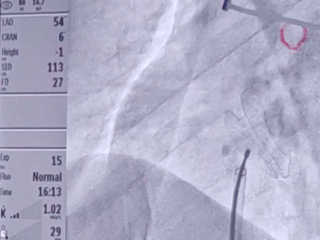

房间隔缺损封堵

将导管送入左上肺静脉

输送输送鞘

输送封堵器

双孔房缺,术前彩超报两孔分别7.9mm和15.0mm,孔距6.3-8.4mm,选择MemoCarna氧化膜房缺封堵器DMFQFDQ-I 28,封堵后仍有2-3mm残余分流,对血液动力学没有影响,术者评估在允许范围

释放房缺封堵器

术后观察封堵器形态

房缺封堵器稳定夹持房间隔